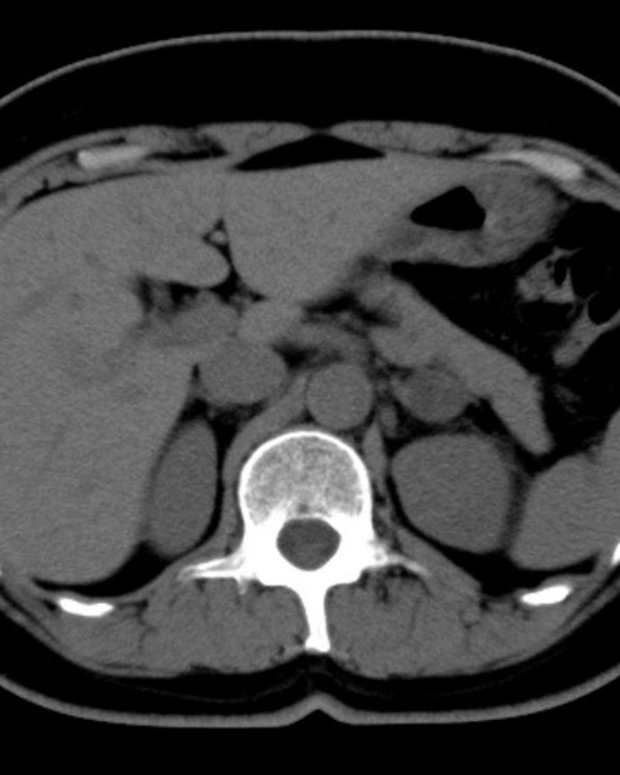

CT scan of the abdomen and pelvis. (a) Imaging without i.v. contrast Ct Scan With Or Without Contrast  Ct without contrast for screening. Here is an overview of the indications for contrasted ct: The dye appears bright on images. So it makes certain areas of the body that are being scanned show up better. In fact, this happens in most cases where a ct scan is needed to diagnose traumatic injuries or a stroke. If needed, you can. Ct Scan With Or Without Contrast.